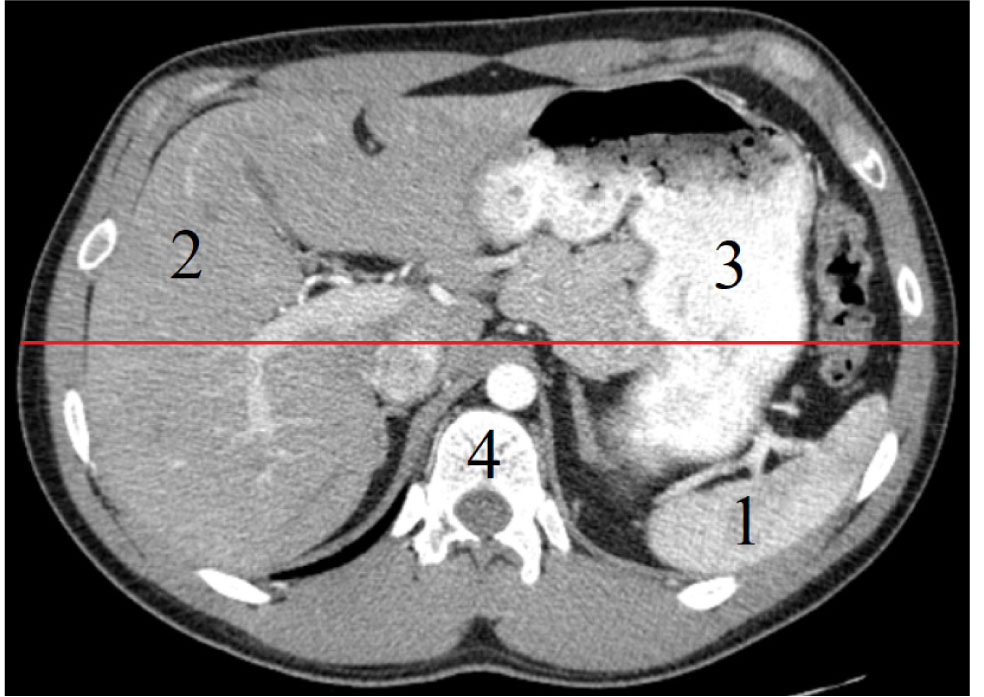

Селезенка определялась при мультиспиральном компьютерно-томографическом исследовании в аксиальной и фронтальной проекциях в виде относительно гомогенного органа полулунной формы с четкими ровными контурами. При исследовании с контрастным усилением визуализировались селезеночная артерия и селезеночная вена, которые выполняли роль ориентиров при поиске ворот селезенки. Хорошо определялись окружающие органы, такие как желудок, поджелудочная железа, ободочная кишка, левая доля печени. Селезенка располагается глубоко в левом подреберье и занимает как верхний, так и нижний этаж брюшной полости. Было установлено, что задний полюс селезенки во всех наблюдениях занимал исключительно верхний этаж брюшной полости, в то время как передний ее полюс располагался в нижнем этаже или находился на границе верхнего и нижнего этажей брюшной полости, в крайних вариантах определялся и в верхнем этаже. Селезенка полностью находилась в пределах верхнего этажа брюшной полости в 12 (10,9 %) случаях, в 46 (41,8 %) наблюдениях занимала верхний этаж и располагалась на границе верхнего и нижнего этажей брюшной полости, а в 52 (47,3 %) – определялась как в верхнем, так и в нижнем этаже брюшной полости. Касательно расположения в дорсо-вентральном направлении селезенка имеет тенденцию находиться в заднем отделе брюшной полости, что показано на компьютерной томограмме брюшной полости и забрюшинного пространства в аксиальной проекции (см. рис.).

Рис. Компьютерная томограмма органов брюшной полости и забрюшинного пространства в аксиальной проекции: 1 – селезенка, 2 – печень, 3 – желудок, 4 – позвонок. Красной линией обозначено деление брюшной полости на передний и задний отделы